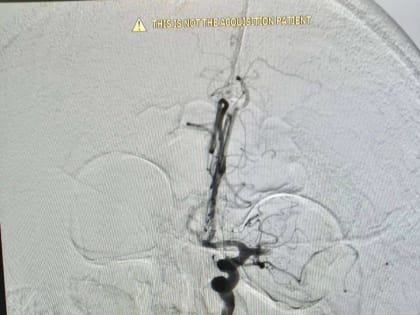

В городской больнице Орска успешно прооперировали 74-летнего мужчину с ишемическим инсультом.

При помощи современных технологий ему удалили тромб в внутримозговой артерии.

В Орске врачи городской больницы спасли 74-летнего местного жителя от ишемического инсульта.